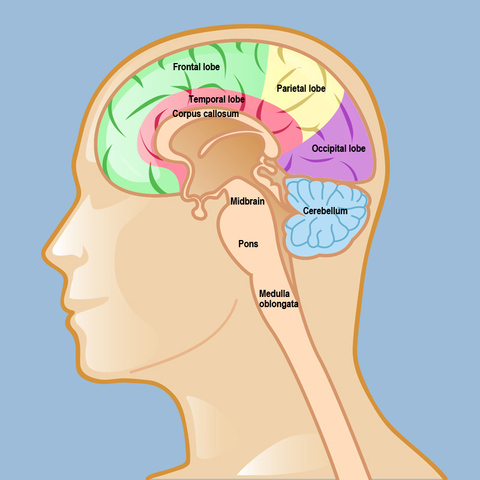

A l'âge de deux ans, le cerveau est de 80% de son poids adulte. L'enfance commence à développer et découvrir, la perception, le mouvement volontaire, les raisonnements, les émotions, la planification et la mémoire du travail au cours des premières années. Lorsque l'enfant est atteint l'âge de six ans, le cerveau est de 95% de sa taille. Pour éviter des problèmes psychologiques de l'enfant, il est important de bâtir un environnement saine et calme. Il faut fournir une communication ouverte.

Au cours de ces années, le tissu adipeux qui entoure les neurones augmentent, le cortex pré frontal est la dernière a maturité, ce qui aide à la prise de décision. Les psychologues expliquent que les adolescents sont sexuellement active et ont l'urgence de prendre des décisions irrationnelles. Toutefois, les adolescents doivent apprendre  à gérer leur comportement irrationnel et irritable. Ainsi, d'éviter les drogues, rapports sexuels non protégés et l'abus de substances.

Le cerveau atteint sa puissance maximale à l'âge de 22 ans et s'étend sur  exactement une demi-décennie. Par la suite, elle minimise la puissance après l'âge de 34 ans. Les fonctionnalités du cerveau du contrôle exécutif se produisent dans le cortex pré frontal et temporelle. La meilleure approche de rester en santé est d'apprendre des nouvelles choses, rester physiquement actif, éviter les toxines les alcools ainsi que les drogues.

Après que le cerveau atteint sa puissance maximale. Les cellules du cerveau est perdu dans  plusieurs domaines critiques telle que l'hippocampe responsable du traitement des souvenirs., alors il commence à rentrer dans le stage d'oubliasse. Par contre, manger une alimentation saine, la pratique de médiation ainsi que l'exercice physique améliore le raisonnement et la concentration abstrait.